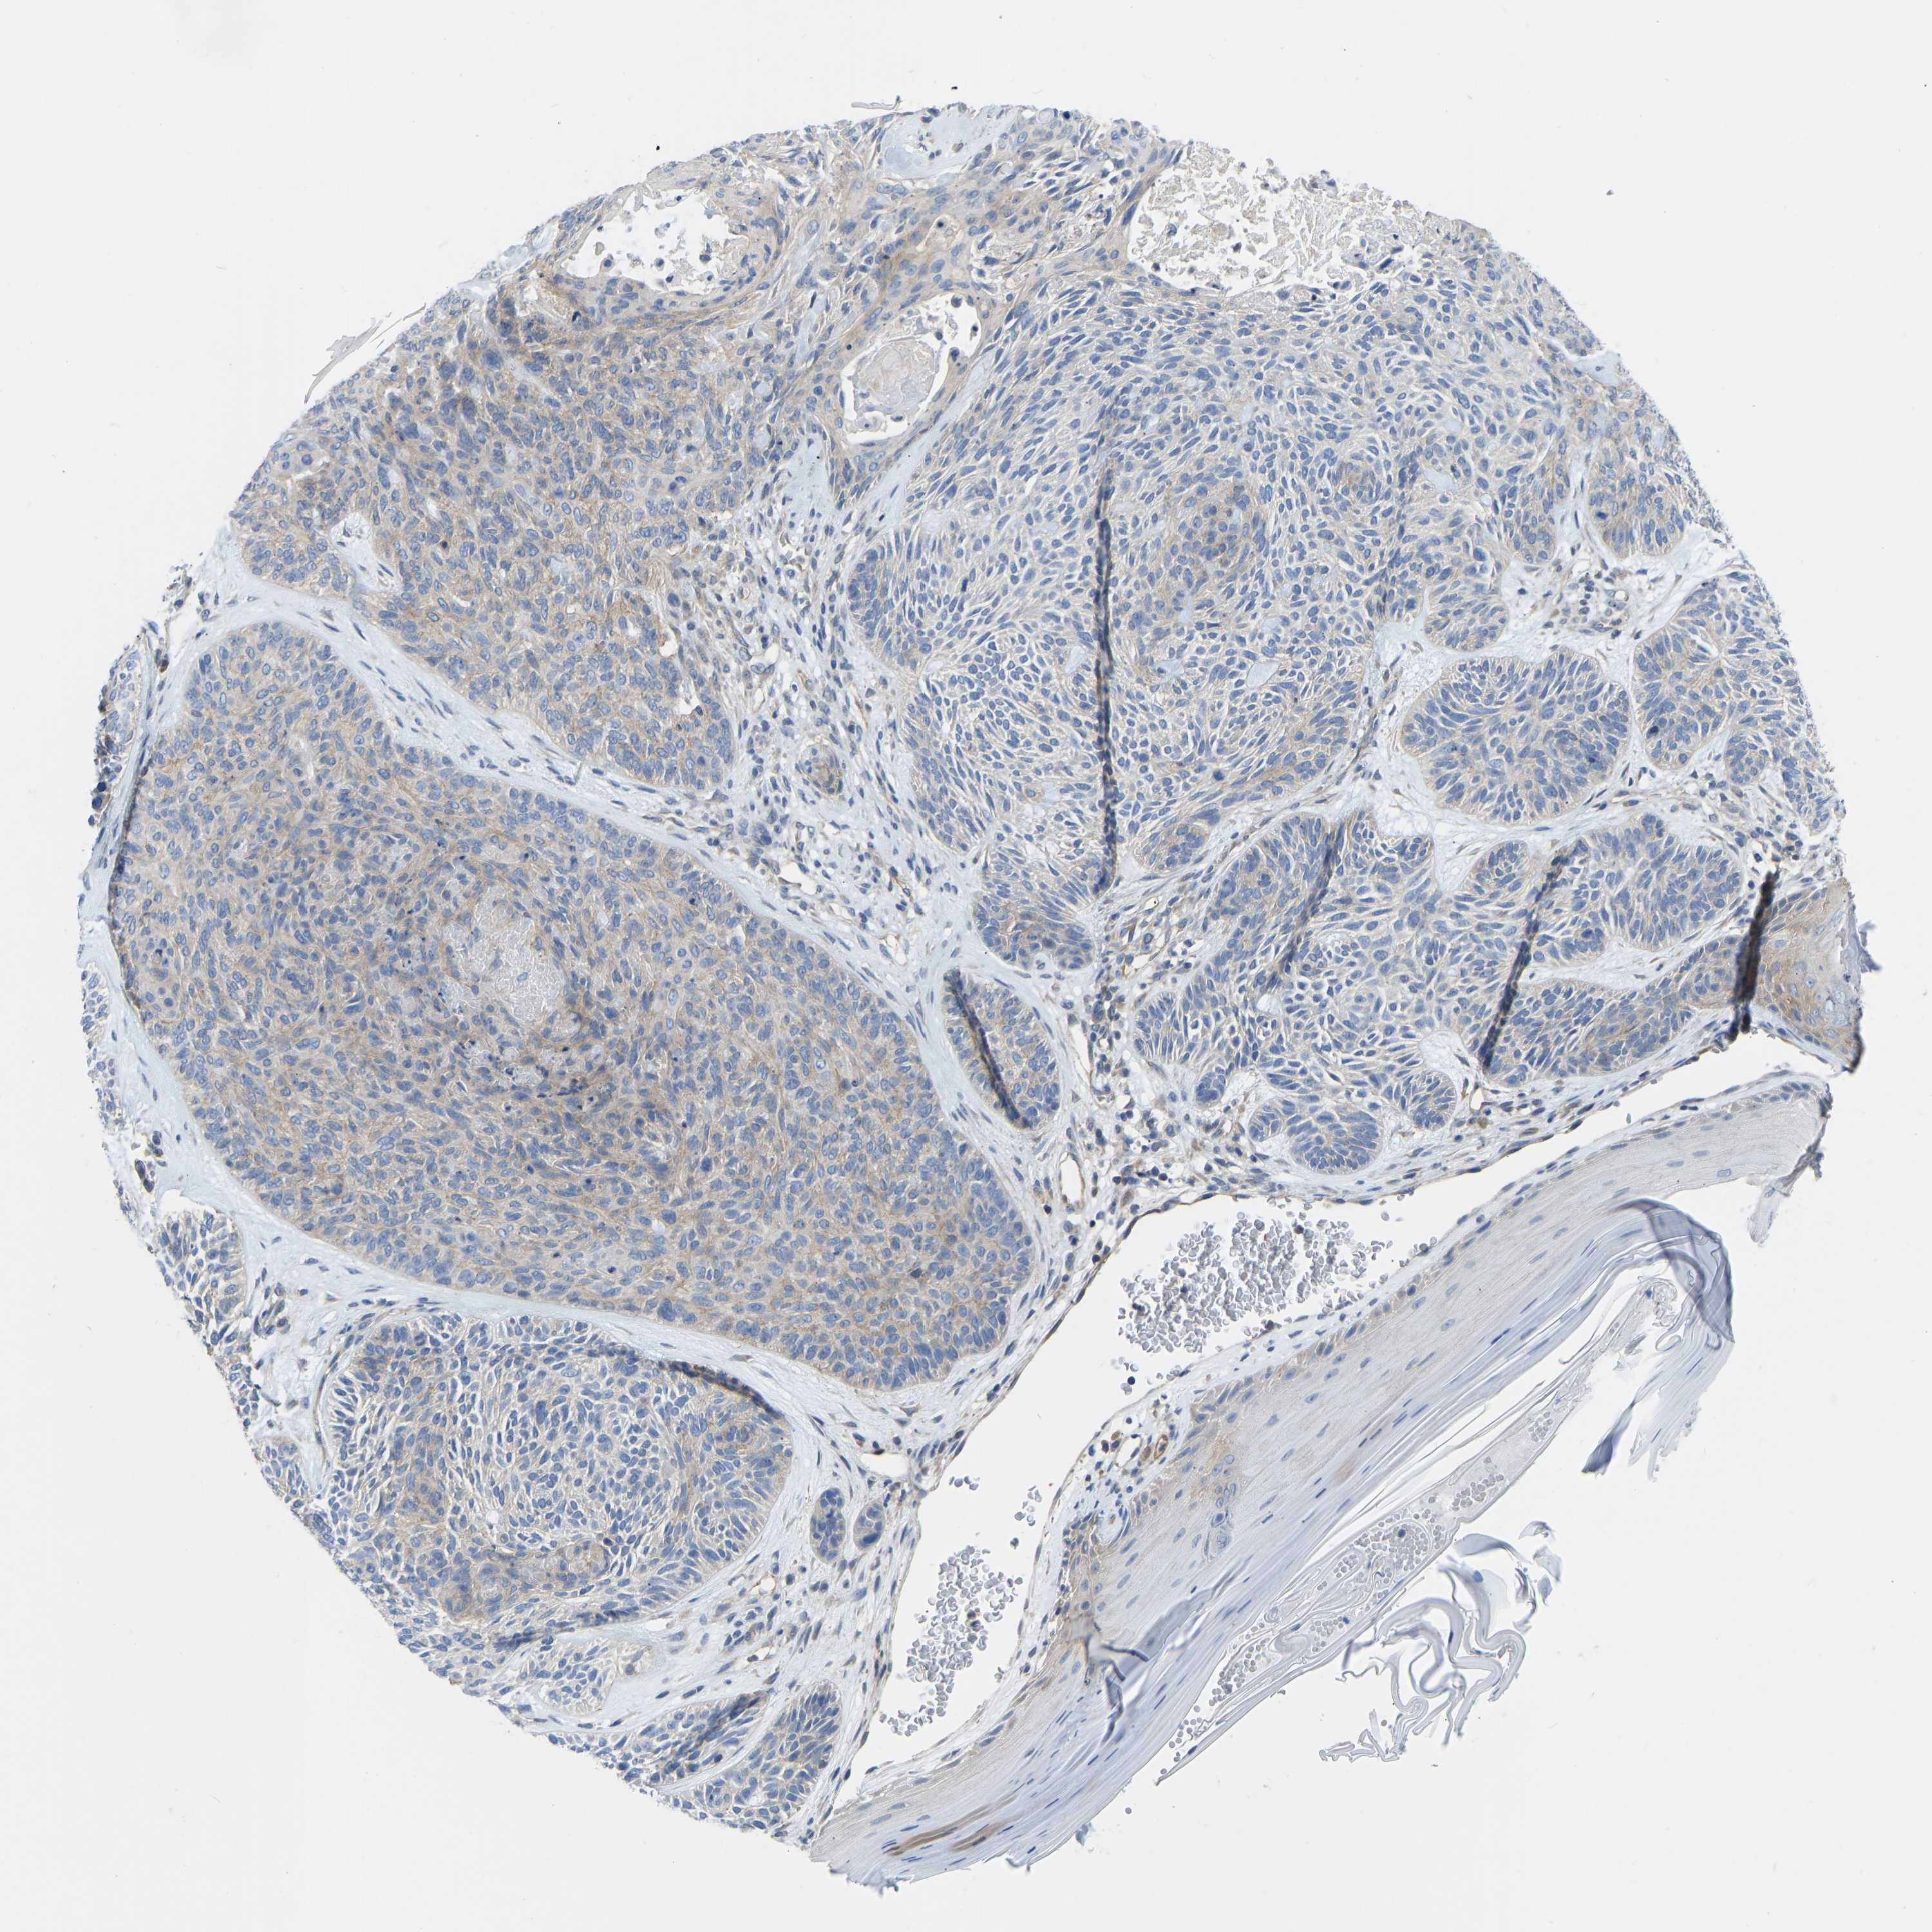

SKIN CANCER - Protein expressioni

A mouse-over function shows sample information and annotation data. Click on an image to view it in a full screen mode. Samples can be filtered based on level of antibody staining by selecting one or several of the following categories: high, medium, low and not detected. The assay and annotation is described here.

Each image is clickable and will lead to virtual microscopy that enables deeper exploration of all samples and also displays staining intensity scores, fraction scores and subcellular localization as well as patient and tissue information for each sample.

Antibody CAB018581

Squamous cell carcinoma, metastatic, NOS